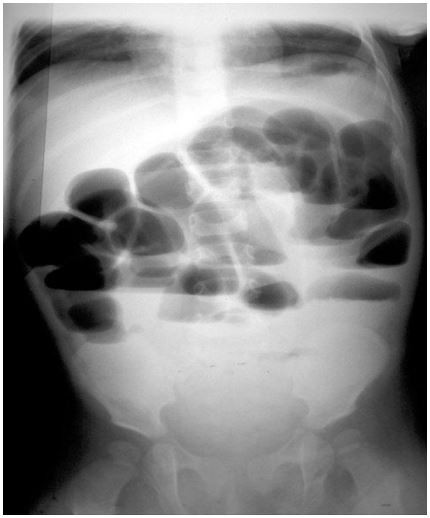

Menino, 4a, sem queixas anteriores, é atendido no pronto socorro, afebril, com dor abdominal intensa, tipo cólica, acompanhada de vômitos biliosos e parada de eliminação de gases e fezes. Realizou este radiograma de abdome em ortostática. Qual é a hipótese diagnóstica mais provável?

Provas